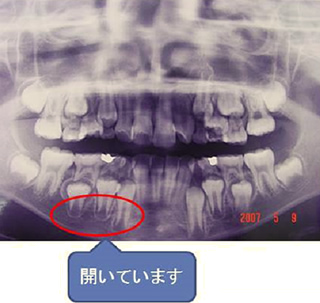

下の写真はスペースが無いので歯が並びません。萎縮してしまっているのです。

当院の矯正治療方法は、この萎縮してしまっている顎の骨ではなく歯を支えている歯槽骨という部位を拡大していきます。